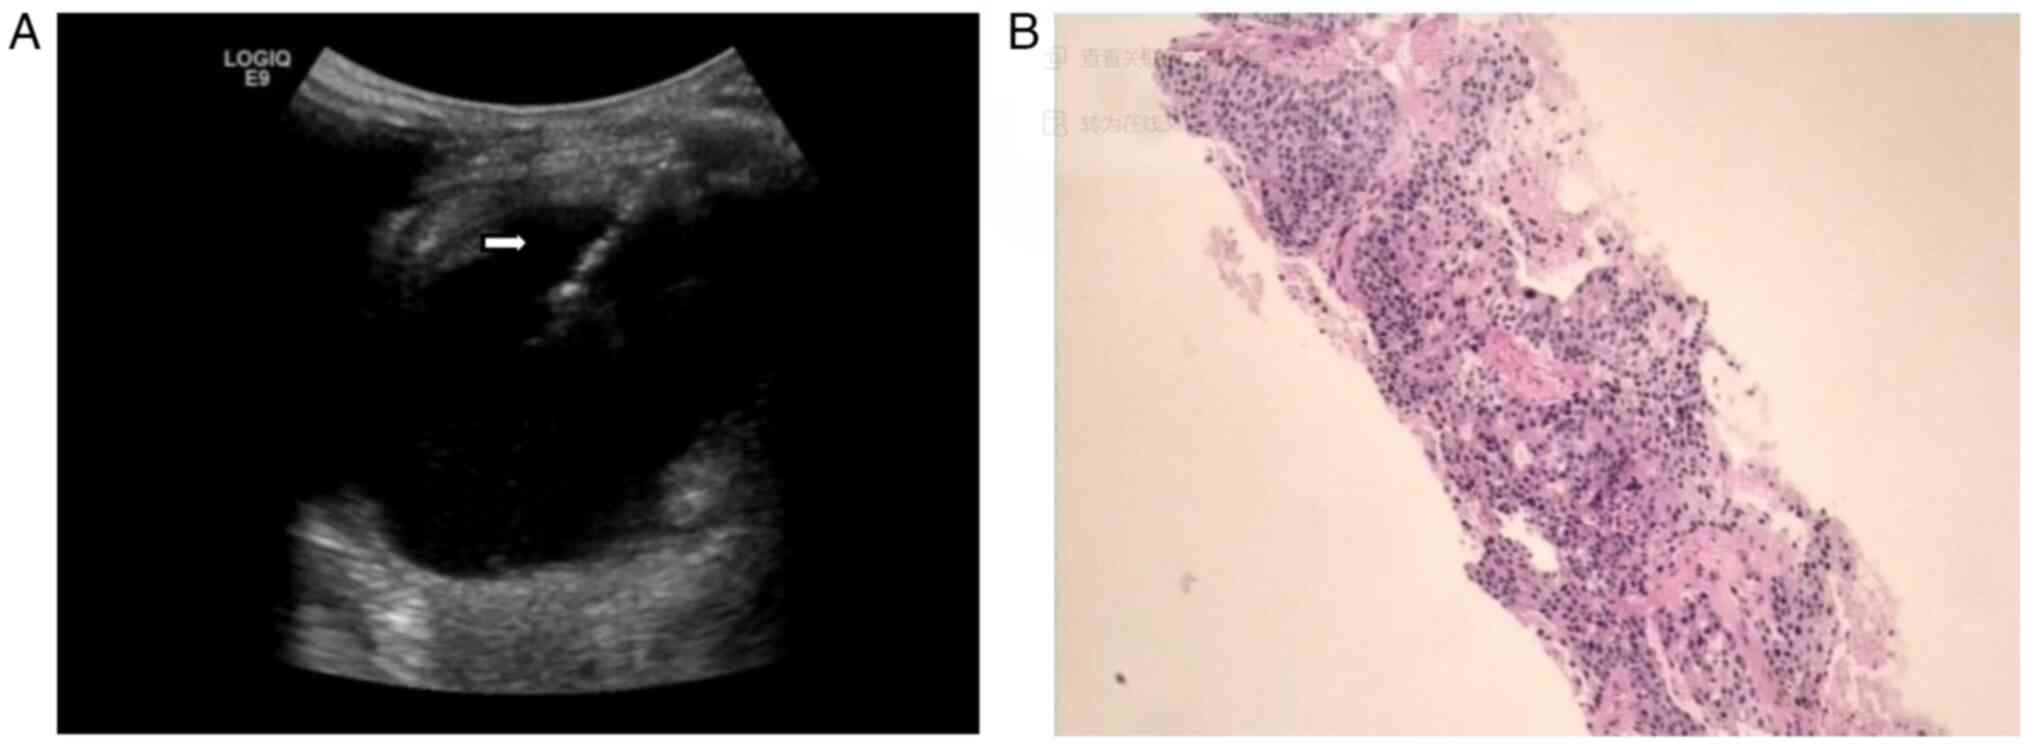

The patient underwent an immediate emergency ultrasound (US) examination (Fig. 1), which detected a 116×91-mm cystic and solid mixed-echo mass in the residual spleen under the left diaphragm. The mass was surrounded by a 22.5-mm thick hypoechoic rough wall (Fig. 1A). Blood flow was detected in the surrounding wall (Fig. 1B). An ultrasonic median longitudinal abdominal scan found that the mass was close to the left lobe of the liver (Fig. 1C), and a xiphoid downward oblique scan found that it was positioned anterior to the abdominal aorta (Fig. 1D). The patient was initially diagnosed with a splenic abscess and treated with anti-inflammatory therapy (cefotaxime 2.00 g diluted in 100 ml 0.9% sodium chloride injection, intravenous drip twice a day), but the abdominal pain was not relieved.

Figure 1.

Ultrasonographic findings. (A) Ultrasonography detected a heterogeneous echo mass in the residual spleen under the left diaphragm with thick hypoechoic peripheral wall. (B) Color Doppler ultrasonography demonstrated a blood flow signal. (C) An ultrasonic median longitudinal abdominal scan found that the mass was close to the left lateral lobe of the liver. (D) An ultrasonic xiphoid downward oblique scan found that the mass was anterior to the abdominal aorta. LL, left lateral lobe of the liver; AO, abdominal aorta.

The patient was placed lying on their right side, with routine disinfection, ultrasonic point selection and positioning. Local anesthesia was applied using 2% lidocaine hydrochloride and an incision was made into the skin subcutaneously. Two percutaneous splenic mass biopsies were taken from different regions of the mass (Fig. 4A). The biopsy samples were immediately fixed with 3 ml 10% neutral buffered formalin fixative at 25°C for 12 h and sent for pathological examination. Percutaneous catheterization and drainage with an 8F pigtail needle was performed in the cystic region of the mass, and dark brown liquid was drawn out. There was no obvious bleeding during the operation and the patient's vital signs were stable. A total of 667 ml of dark brown liquid was drained out. The results of the drainage fluid culture showed hemolytic Staphylococcus. The pathological diagnosis of the biopsy was provided by the Department of Pathology, Shaoxing Second Hospital. The pathological examination was performed on 3-µm sections, which were stained with and hematoxylin and eosin at 70°C for 30 min and were observed under a light microscope (magnification, ×50). The result (Fig. 4B) showed that the splenic puncture tissue came from a SCC metastasis of medium-low differentiation, composed of sheets of large polymorphic cells exhibiting intercellular bridges and keratin pearls.